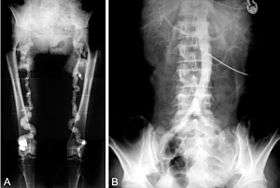

![]() B. Translumbar aortography shows near-total obstruction of the femoral arteries in a patient with Monckeberg's arteriosclerosis. | |